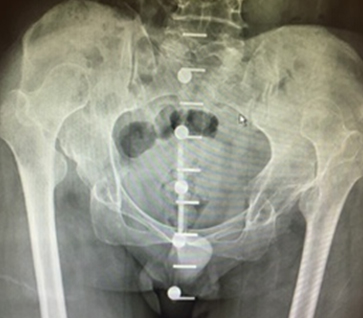

Some hips present with complex deformities. Examples are shown below. These hips often have had previous surgery resulting in severe stiffness or anatomical deformities. Others have significant congenital abnormalities like hip dislocation.

Careful pre-operative planning is done often using the OPS software analysis and an operative plan developed with attention to implant positioning and implant types. Surgery is performed via the posterior approach. Occasionally extra bone graft is required to the pelvis/acetabulum or even femoral bone shortening (in high congenital hip dislocation).

These are examples of complex hip replacements: